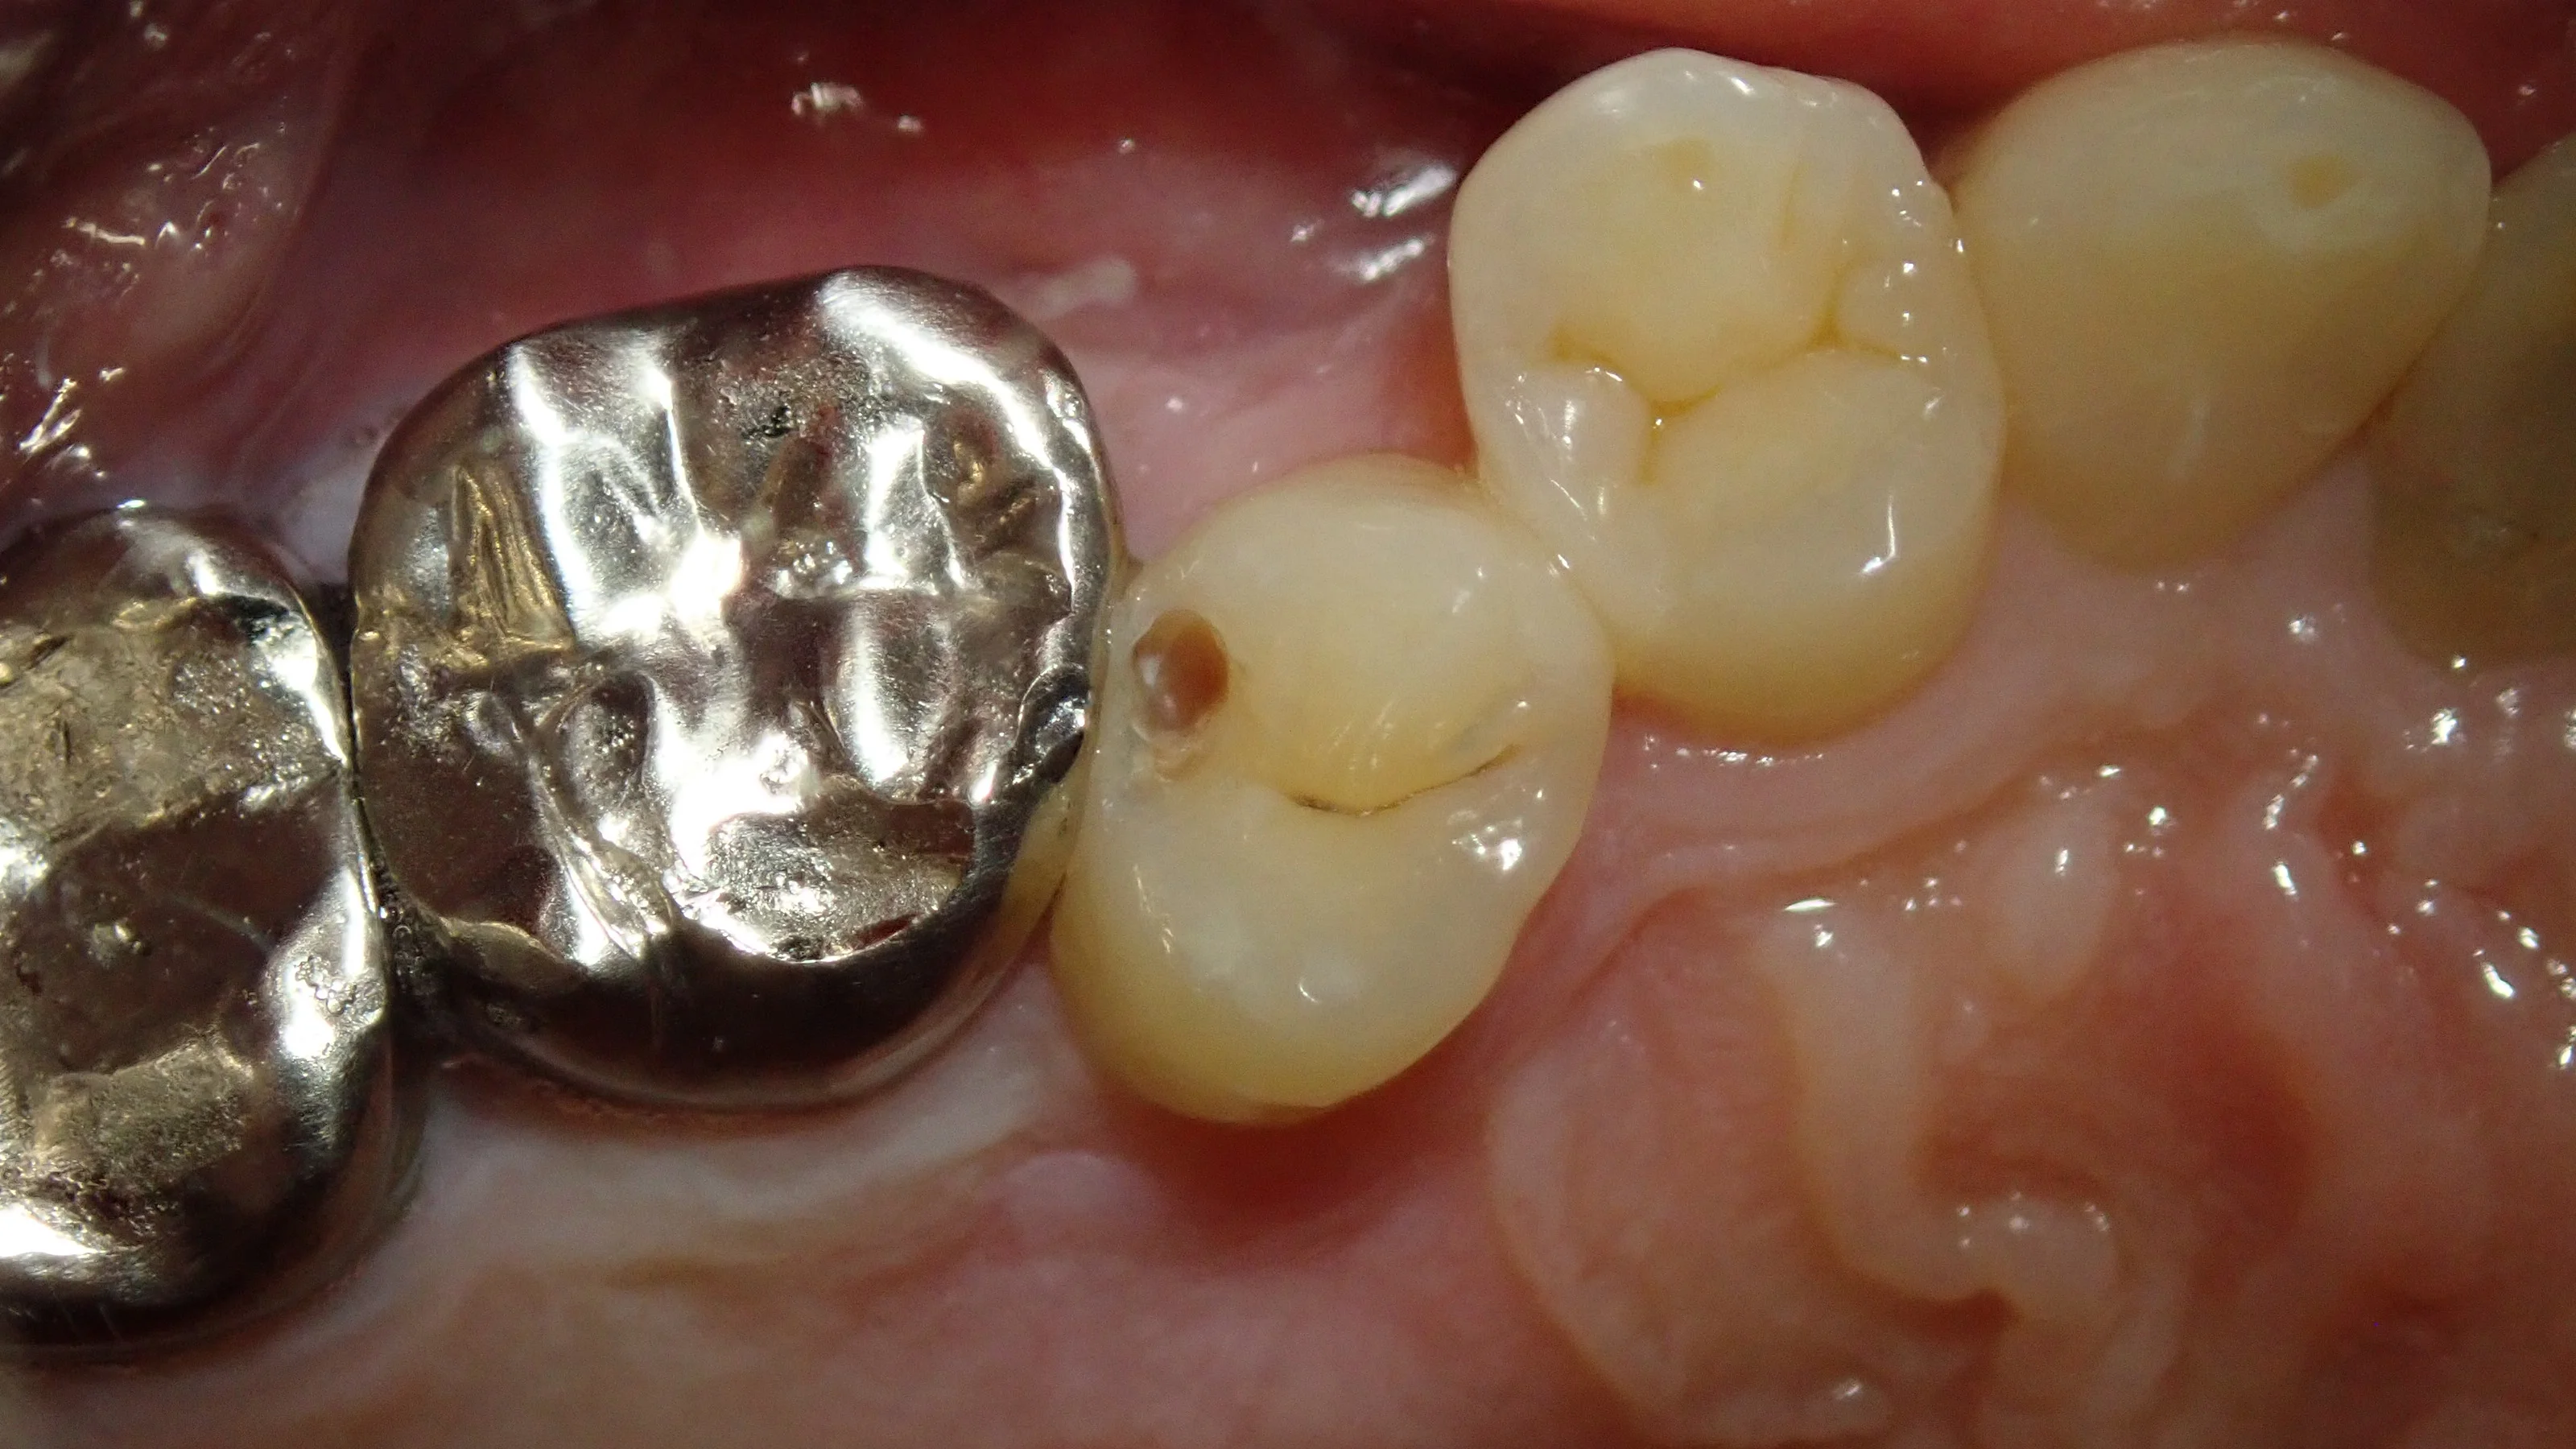

取りきったのがこちらです。

真ん中の歯は神経ギリッギリになってしまっていましたね・・・。

左側の歯に関しては、少し前のQ&Aで書きましたが・・・

麻酔が効ききる前に施術に入ってしまい、閾値が下がってしまいました・・・。

そのため、この日のこれ以上の処置が出来なくなってしまったため、虫歯を取りきらずにひとまず埋めることになってしまいました・・・施術を2回に分けることになってしまい、申し訳ありません。